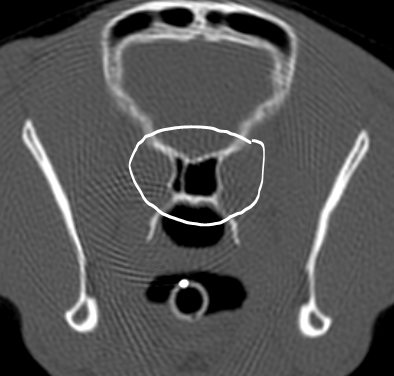

What are these structures?

Caudal circumflex humeral artery

Axillobrachial vein

These are branches of the axillary artery and vein